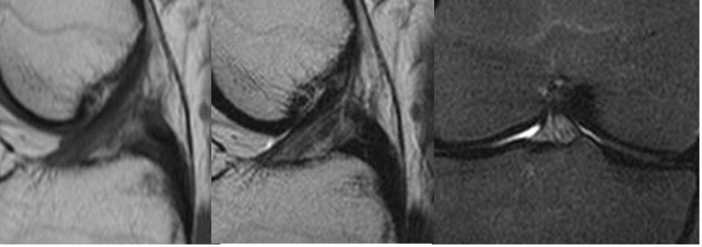

Fig 96. Ruptura subaguda del LCA.

A: RM sagital en T1, B: RM sagital en T2 y C: RM sagital en STIR. LCA horizontalizado, por ruptura en su origen femoral.